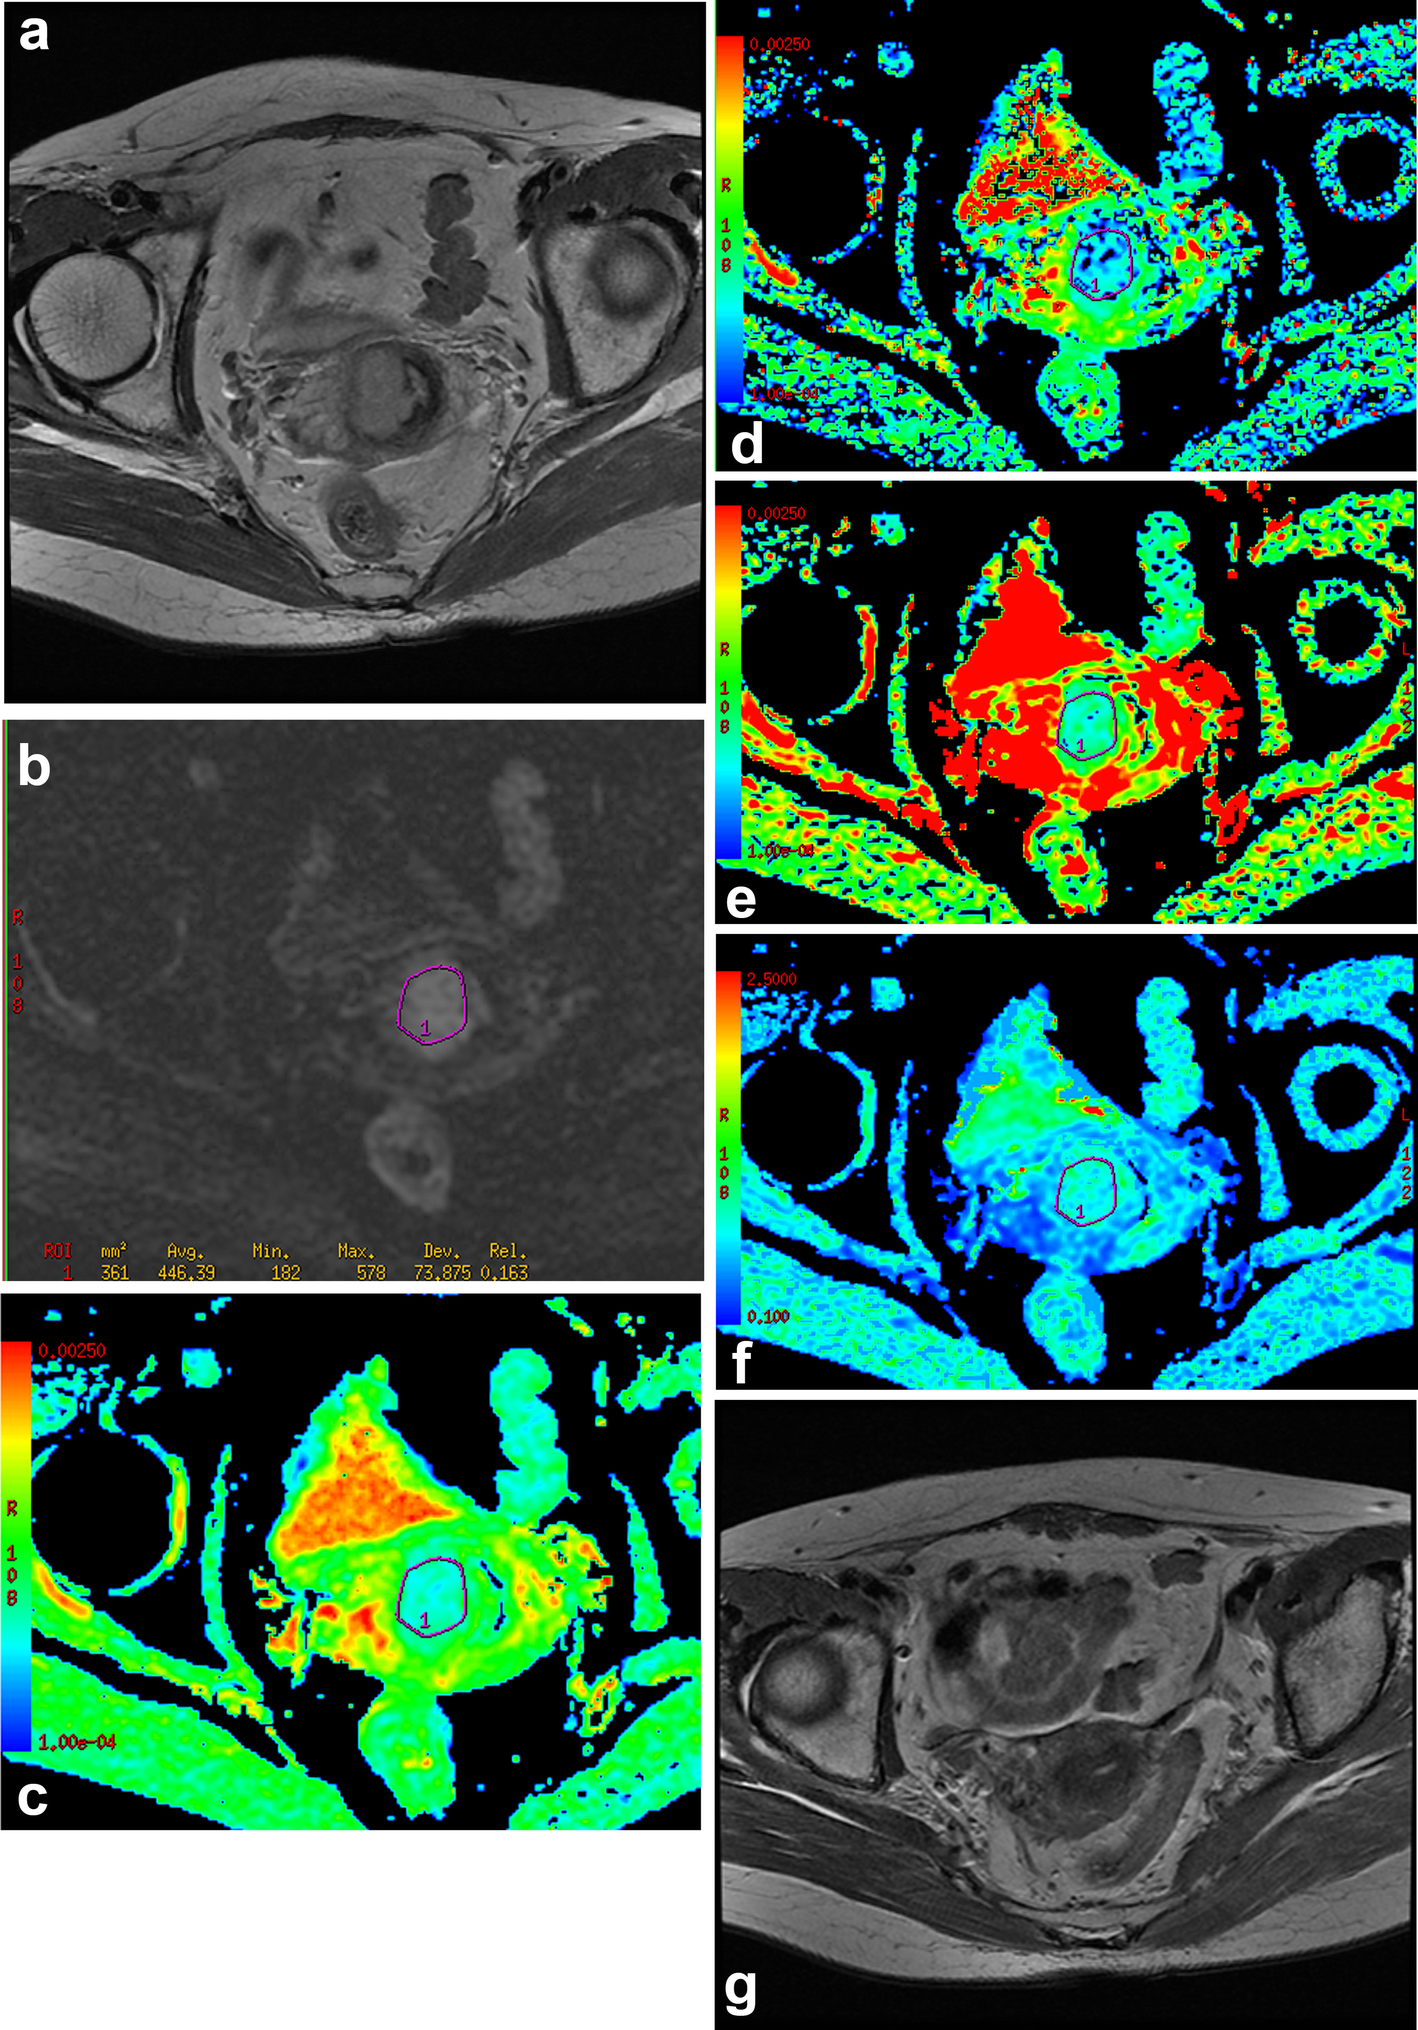

Fig. 2

The mean value of DDC in responders group. a Axial T2WI, there was an irregular mass in cervix. b DWI (b = 800 s/mm2), the image showed the location of ROI during the tumor area. c ADC map, the final ADC value was low (=0.619 × 10− 3 mm2/s). d D map, the final D value was low (=0.608 × 10− 3 mm2/s). e DDC map, the final DDC value was low (=0.972 × 10− 3 mm2/s), which was lower than the cut-off value of DDC (=1.141 × 10− 3 mm2/s). f α map, the final α value was high (=0.910). g Seven months after radiochemotherapy, the lesion disappeared completely; the patient was classified as responders group